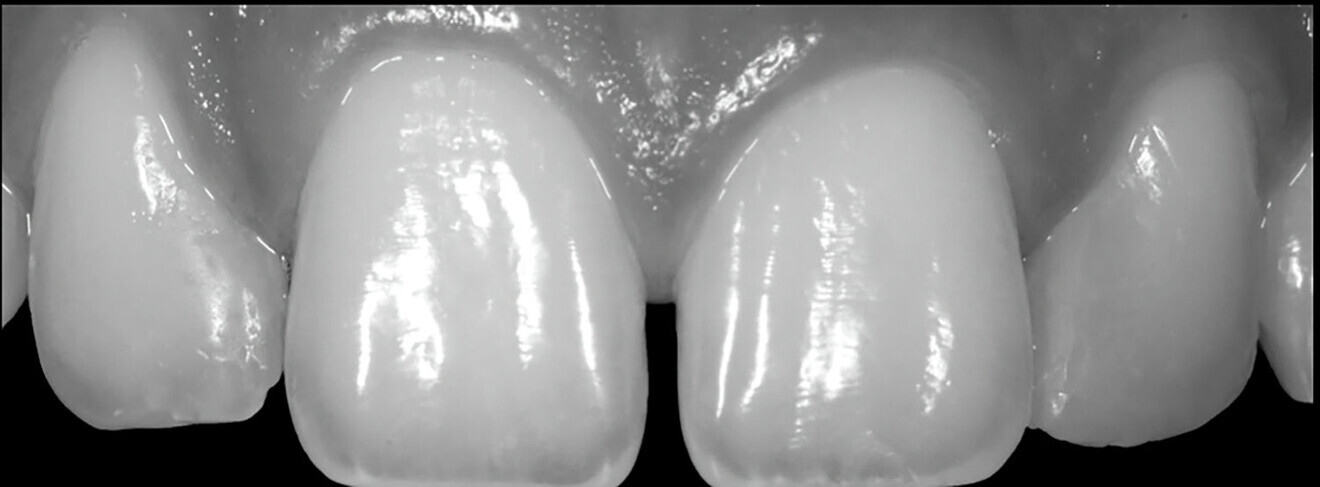

We followed a thorough analysis of the chromatic spectrum, as described by Naorungroj, to accurately and precisely establish the shades to be used in the operative steps (Fig. 2).1 The photographic material was carefully analysed to determine the ideal work planes to gain the information required to achieve the ultimate aesthetic aim of the treatment.

Figs. 2a–d: Choice of shade values.

Fig. 2b

Fig. 2c

Fig. 2d